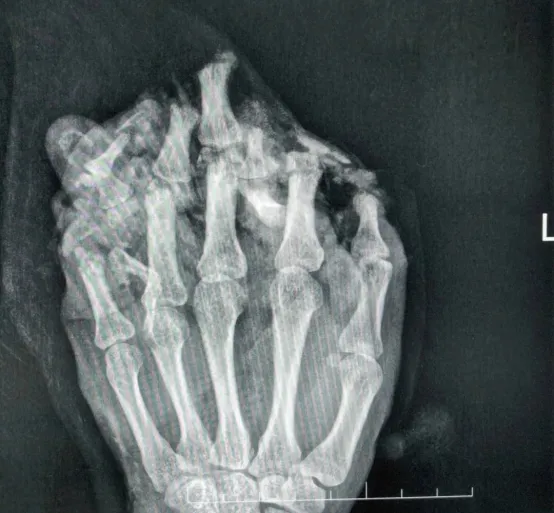

(拍片显示左手伤情严重)

据了解,事发当天,小王在工作时操作不慎,左手被机器碾压,瞬间出现手掌、手背及多根手指皮肤脱套流血、剧烈疼痛的症状,被同事紧急送往东莞市横沥医院救治。经医生详细检查及拍片确诊,小王的左手伤情极为严重,涉及六大类损伤,包括手掌手背及多根手指皮肤毁损脱套伤、肌腱神经血管损伤、多发性开放性指骨骨折伴毁损,以及左拇指相关皮肤、神经、甲床损伤等,手部功能面临严重丧失风险。